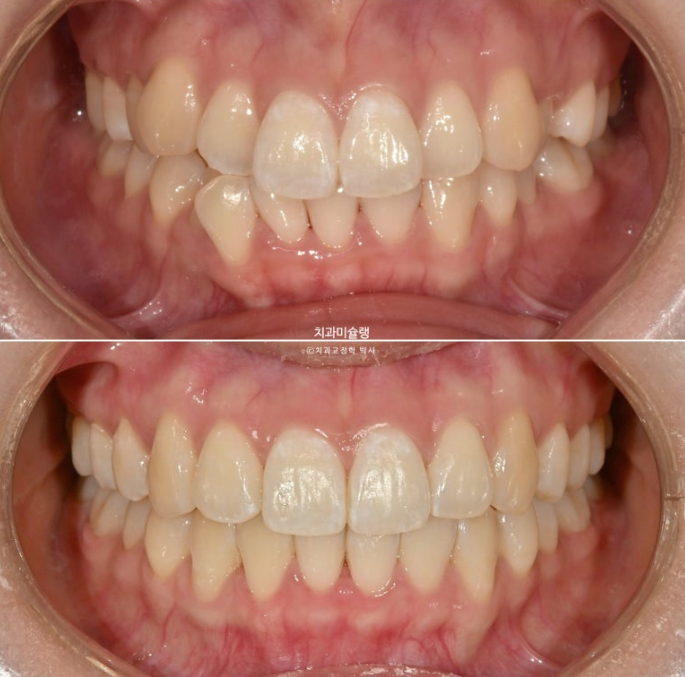

오늘은 비발치 교정 사랑니 공간을 이용하여 덧니와 중심선, 가위교합을 개선한 증례를 보여드리겠습니다.

이제 전 후 비교 보겠습니다.

총 치료기간은 1년 8개월 재제작은 1회 했습니다.

24.02~25.10

개선된 덧니와 가위교합